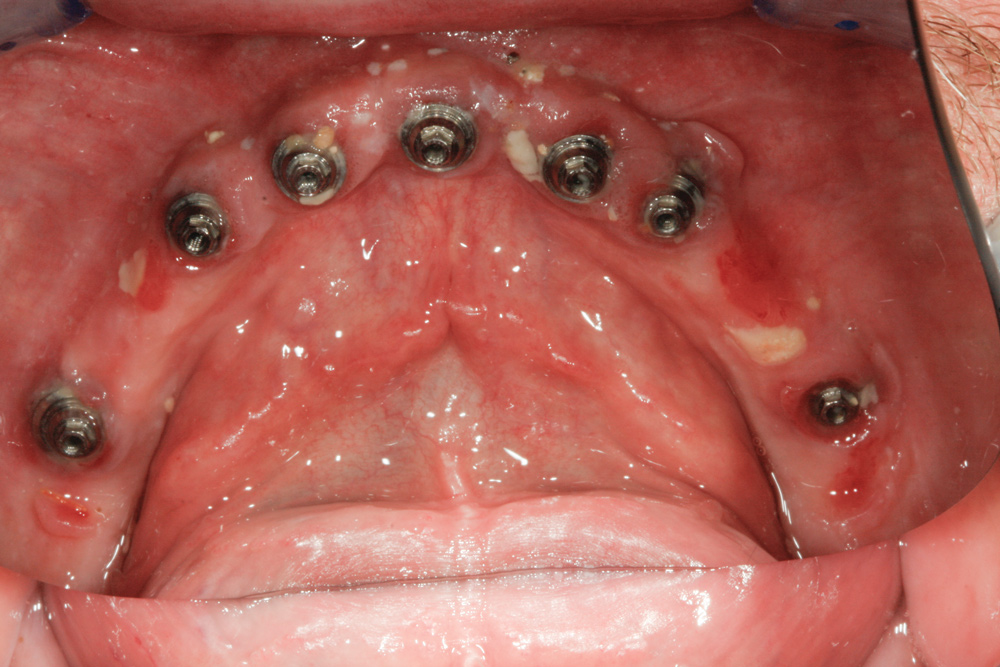

The Intaglio Surface

Long-term health and longevity of the implants rely highly on, among other things, having the proper intaglio surface. The ridge-lap design should be avoided. Even though zirconia is highly conducive to healthy tissue, if a ridge-lap design is made, cleaning is not predictable, as shown in Figure 3 and Figure 4. The tissue is not healthy, and mucositis, bleeding, calculus, and food can be detected. In a case in which a ridge-lap design must be done, a removable type of denture would be better for ease of removal and cleaning.6

Fig 3. These pictures illustrate what happens when the proper type of intaglio surface is neglected.

Figure 3

Fig 4. These pictures illustrate what happens when the proper type of intaglio surface is neglected.

Figure 4